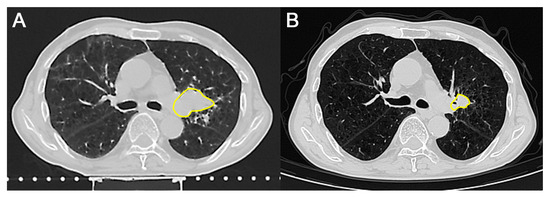

Background: Minimally invasive techniques for living donor nephrectomy are crucial for donor safety and promoting organ donation. Hand-Assisted Retroperitoneoscopic Donor Nephrectomy (HARP-DN) combines the benefits of minimally invasive surgery with...